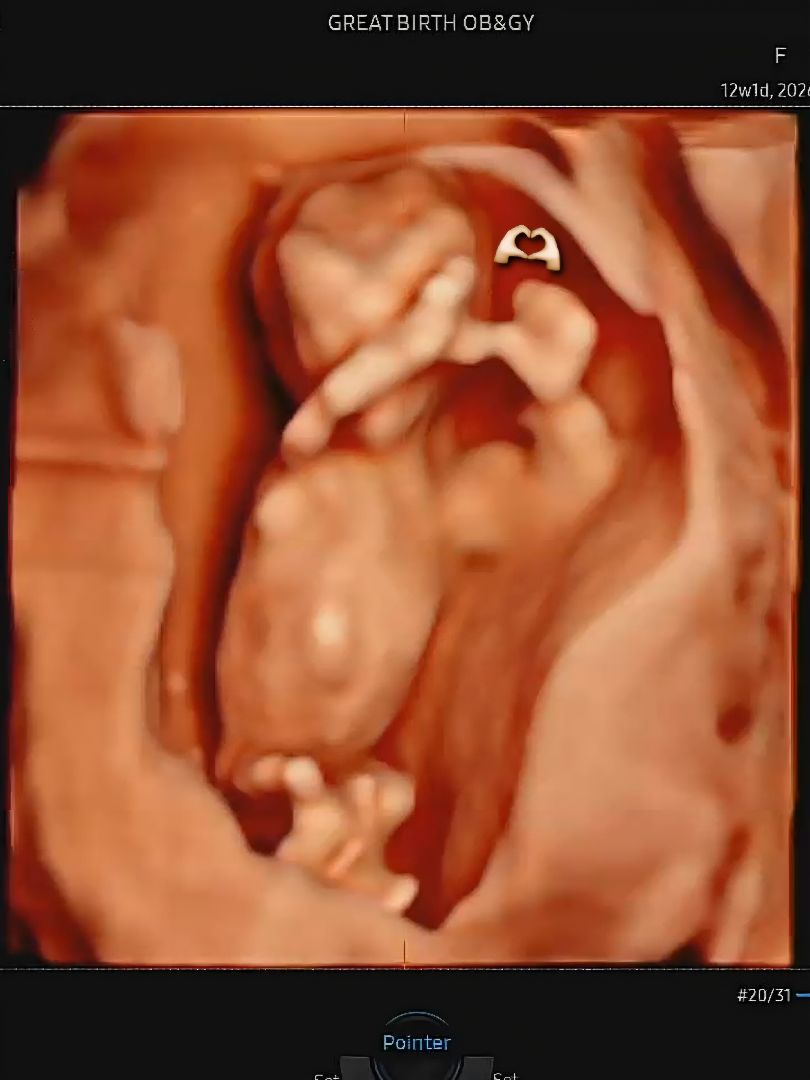

12주차 손하트하고 있는 아기 보고 가세요 👶🏻🤍

오늘 12주 1일차 기형아 검사 & 입체 초음파 보고 왔어요 :) 6.6cm로 13주 크기로 잘 크고 있고, 양수 안에서 아주 잘 놀고 있더라구요 ! 이 시기에는 도라에몽 손으로 보이는 경우가 대부분인데, 저희 애기는 손가락이 선명하게 잘 보여서 초음파 선생님도 놀라셨어요 ㅎㅎ 특히 손하트 하고 있는 모습이 너무나 사랑스럽지 않나요 ㅠ 세상에 ㅠㅠㅠ 🤍🤍🤍🤍🤍 14주 이후 되어야 성별이 명확해진다고 하는데, 각도법상 딸일 것 같은 느낌이 딱! 드네요 :)